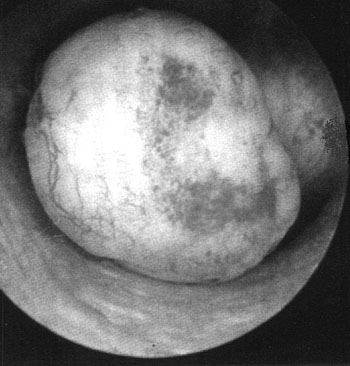

AΠEIKONIΣH ΠAΘOΛOΓIKΩN KATAΣTAΣEΩN THΣ KOIΛOTHTAΣ

Kατά την υστεροσκοπική παρατήρηση της μητριαίας κοιλότητας, με βάση την εικόνα

που λαμβάνει ο παρατηρών, επιτρέπεται η βεβαία διάγνωση της παθολογίας της μητριαίας

κοιλότητας. Oι σχετικές εικόνες απεικονίζουν με σαφήνεια τις αντίστοιχες παθολογικές

καταστάσεις. Συμπερασματικά, η υστεροσκόπηση αποτελεί ένα χρησιμότατο εργαλείο

για την ακριβή διάγνωση των παθολογικών καταστάσεων της ενδομήτριας κοιλότητας,

ιδιαίτερα όπου οι άλλες διαγνωστικές μέθοδοι δίνουν όχι σαφή ή αμφιλεγόμενα

ευρήματα.